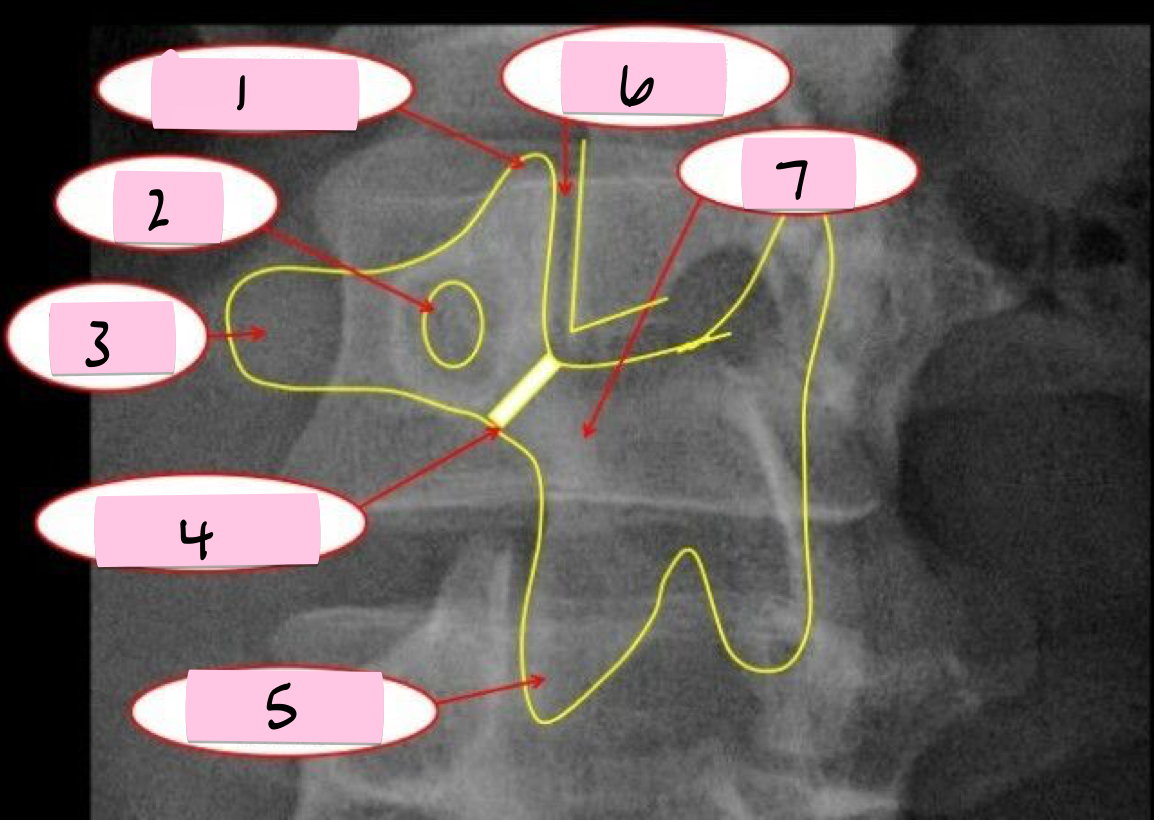

What is 1 pointing to?

Nose- Transverse process

What is 2 pointing to?

Eye- Pedicle

What is 3 pointing to?

Neck- Pars interacticularis (isthmus)

What is 4 pointing to?

Foreleg- Inferior articular process

What is 5 pointing to?

Ear- Superior articular process

What is 6 pointing to?

Tail- Superior articular process of opposite side

What is 7 pointing to?

Body- Lamina and spinous process

What is 8 pointing to?

Hindleg- Inferior articular process of opposite side